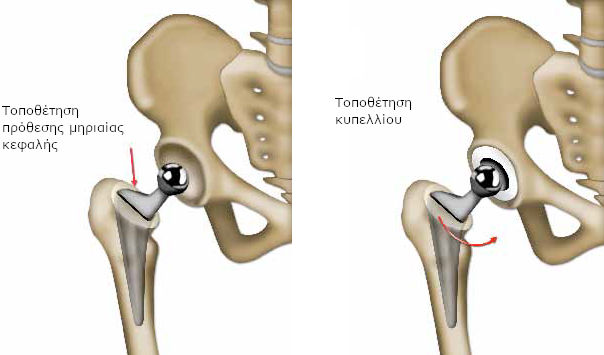

Εάν αντικατασταθεί μόνο η κεφαλή του μηριαίου, η πρόθεση αποτελείται από ένα στέλεχος, το οποίο εισάγεται στο μηριαίο. Στο στέλεχος εφαρμόζει ένα τμήμα με σφαιρικό σχήμα (κεφαλή πρόθεσης). Στην ιατρική γλώσσα, μιλάμε για πρόθεση μηριαίας κεφαλής.

Όταν πρέπει να αντικατασταθούν όλα τα μέρη της άρθρωσης (ολική πρόθεση), ο χειρουργός προσθέτει ένα τμήμα σε σχήμα κούπας (το κυπέλλιο), που στερεώνεται στην κοτύλη.

Στη συνέχεια, ο χειρουργός ενώνει τα δύο μέρη της πρόθεσης και διασφαλίζει τη σταθερή συγκράτησή τους σε όλες τις θέσεις. Τέλος, τοποθετεί στη θέση τους όλα τα στοιχεία που περιβάλλουν την άρθρωση (θύλακος, μύες, κτλ.).